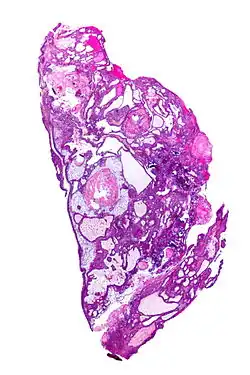

Kraniofaryngeom je pomalu rostoucí typ tumoru, jenž vzniká z embryonální tkáně hypofýzy z Rathkeho výchlipky, nejčastěji u dětí a u věkové skupiny 50–60 let. Představuje asi 4 % intrakraniálních tumorů. Způsobuje poruchy vidění, kvůli tlaku na chiasma opticum.[1][2]